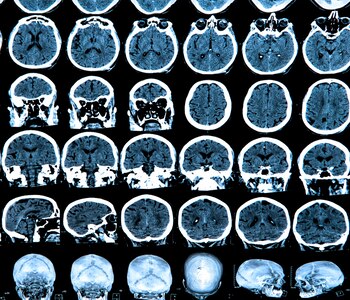

Las personas que se mueven con violencia mientras duermen o actúan sus pesadillas sin despertarse pueden tener un riesgo mayor de sufrir demencia o Mal de Parkinson que aquellas que descansan plácidamente. Según una nueva investigación del experto en sueño John Peever, de la Universidad de Toronto, ciertas alteraciones del sueño pueden ser una señal de alerta para algunas enfermedades neurológicas en más del 80% de los casos.

El investigador canadiense y sus colegas hallaron que el trastorno del sueño REM o paradójico (una de las dos fases, caracterizada por movimientos oculares rápidos y un tono muscular reducido) tiene la capacidad de predecir un diagnóstico de estas dolencias. Gritos, llanto, golpes y patadas mientras se sufren pesadillas pueden anunciar un desorden neurológico 15 años antes de que se presenten los síntomas.

La razón: esos trastornos del sueño tienen su origen en células deficientes del bulbo raquídeo, que se cree que juegan un papel en la aparición de enfermedades como Parkinson o la Demencia de Cuerpos de Lewy, la tercera causa de demencia después del Mal de Alzheimer y la vascular.

La hipótesis de Peever indica que cuando estas células no funcionar correctamente, también influyen en el desarrollo del Parkinson, la demencia y otros problemas del sistema nervioso y del cerebro que se ven en las personas mayores.

"Por alguna razón las células en la zona del sueño REM son las primeras que se enferman", dijo. "Luego la enfermedad neurodegenerativa se propaga por el cerebro y afecta otras áreas".

Poco se sabe sobre por qué las personas sueñan, pero desde la década de 1960 se conoce al menos que ese tronco inferior del cerebro participa en el sueño REM. Peever y sus colegas descubrieron que existen células responsables del estado del sueño, a las que llamaron neuronas REM-activas, y que se las puede controlar, según experimentaron con ratones. "Cuando encendemos estas células, causan un tránsito rápido al sueño REM", dijo en la conferencia anual de la Asociación Canadiense de Neurociencia, realizada el 29 de mayo en Montreal.

El equipo estudió estas alteraciones en seres humanos y descubrió que "más del 80% de las personas que sufren de trastorno del sueño REM terminan por desarrollar sinucleopatías", que son las enfermedades causadas por la toxicidad cerebral de la proteína alfa-sinucleína.

Los resultados, publicados en el estudio Connecting the dots between dreams and brain disease (Atando cabos entre los sueños y la enfermedad cerebral), advirtieron: "Nuestra investigación sugiere que los trastornos del sueño pueden ser una señal temprana de que estas enfermedades pueden aparecer quince años más tarde".

La importancia del hallazgo radica en su posibilidad de abrir la puerta a una estrategia de protección neuronal. "Del mismo modo que vemos que hay personas con predisposición al cáncer, el diagnóstico de los trastornos del sueño REM nos puede permitir brindarles a los individuos acciones preventivas para que se mantengan saludables mucho antes de que desarrollen estas enfermedades neurológicas muy serias".